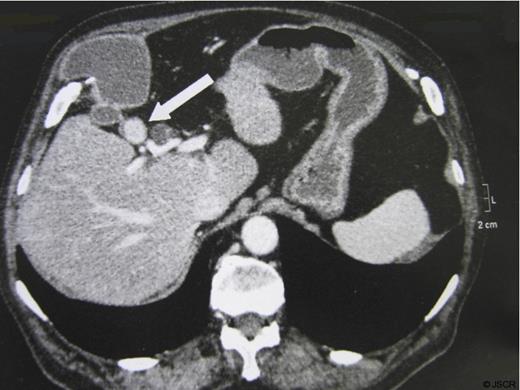

The patient was an 85 year-old man with history of hypertension, previous surgery for perforated diverticular disease (Hartmann procedure followed by reversal of colostomy). He had suffered from occasional pain in the right upper quadrant for several months. The physical examination showed a 5 cm mass in the right upper quadrant tender to palpation. Ultrasound and CT confirmed the presence of a lithiasic gallbladder herniated through the abdominal wall (fig.1), with a dilatation of the common bile duct that measured 11 mm, due to a 17 mm obstructive infundibular stone as it happens in Mirizzi syndrome type I (fig.2).

Another interesting aspect of this case is the presence of a chronically distended gallbladder (gallbladder hydrops), associated with extrinsic compression of the common hepatic duct by an impacted stone in the infundibulum (Mirizzi syndrome type I) (8). It is probably the gallbladder dilatation that plays an important role in the development of the hernia pressing constantly the gallbladder against the abdominal wall. Usually the clinical picture is represented by a right upper quadrant pain, associated with variable degrees of a compromised general condition. In our experience the preoperative study based on computed tomography is essential for the diagnosis of the gallbladder hernia, and it provides also additional information on the abdominal wall defect.